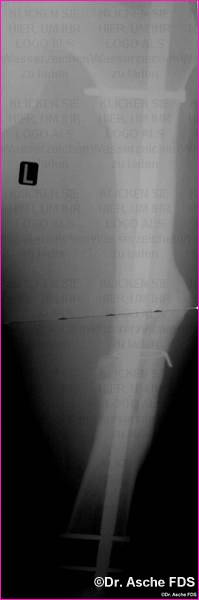

Die unten beschriebene Art der Valgisierung- und Drehosteotomie

wurde vorgenommen.

Die Stabilisierung erfolget mit einem Kompressionsnagel

T2

Nach 3 Monaten war die Fraktur fest verheilt, der Patient

konnte beschwerdefrei laufen

Drehung und Achse waren Korrekt. Auch bei Drehfehlern

von 10° sollte immer wieder die Frage einer Korrektur erwogen werden.